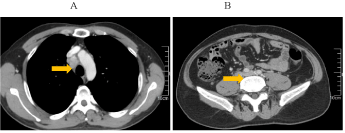

Figure 3. A: enlargement of mediastinal lymph nodes; B: multiple enlarged retroperitoneal lymph nodes were larger than before.